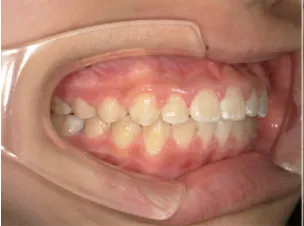

治療後⑤中2:治療終了

| 行ったご提案・診断内容 | 生え変わりが終わってなくマルチブラケット法による咬合治療には早い時期のため、顔立ちの成長を促す目的で歯列弓(アーチ)の拡大と前歯を並べながら永久歯が生えるのを待ち、咬合治療開始時に再診断で抜歯、非抜歯を最終検討する提案をしました。 再診断時(写真②)、歯列の拡大と上顎前歯の並べ替えはされていましたが八重歯となったため抜歯、非抜歯を検討しました。 口元は特に問題がなく非抜歯で八重歯を改善するためのスペースを作ることが可能なため非抜歯治療を提案しました。 治療は、 ・拡大および上顎左右6を遠心移動させてスペースを作る 予定装置 |